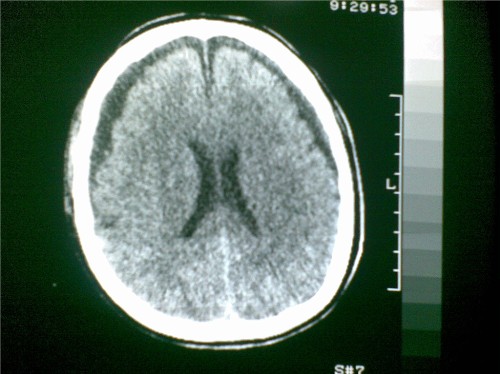

标题: CT28096:男,75岁,外伤10天后,现在恶心、呕吐。是硬膜下积 [打印本页]

标题: CT28096:男,75岁,外伤10天后,现在恶心、呕吐。是硬膜下积

硬膜下积液、右侧基底节、左侧放射冠腔梗。

硬膜下积液、多发性腔梗。

1)双侧额颞顶部硬膜下积液;建议必要时复查。2)多发性腔隙性脑梗塞。